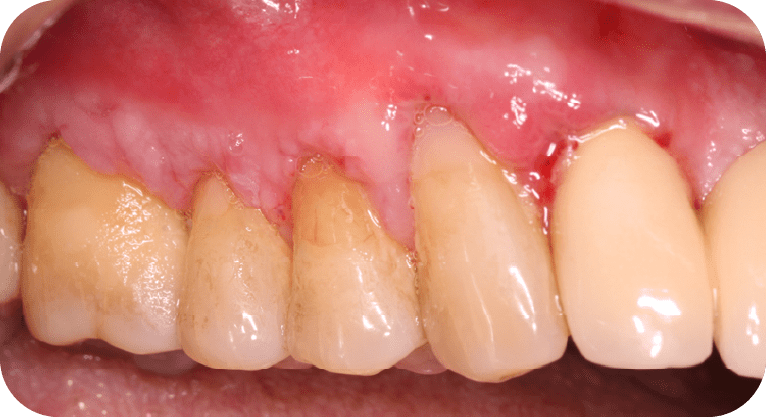

Male patient, “65” years old

Treatment: Gum surgery

The patient had dental sensitivity caused by exposed tooth roots, so a root coverage surgery with a gum gra and gum repositioning was performed. This procedure protected the exposed roots, reduced hypersensitivity, and improved both periodontal function and aesthetics, achieving satisfactory results for the patient.